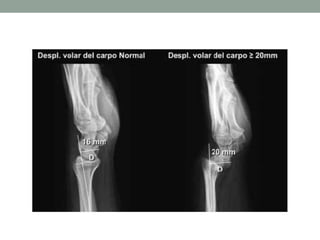

Diagnóstico Imagenológico

• McCarroll et al. 2010

• Tilt ulnar

• Subsidencia del semilunar

• Angulo de la fosa semilunar

• Desplazamiento volar del carpo ≥ 20mm

• Distancia entre el eje de la ulna y el punto

más volar del semilunar o escafoides

Diagnóstico Imagenológico • McCarrollet al. 2010 • Tilt ulnar • Subsidencia del semilunar • Angulo de la fosa semilunar • Desplazamiento volar del carpo ≥ 20mm • Distancia entre el eje de la ulna y el punto más volar del semilunar o escafoides